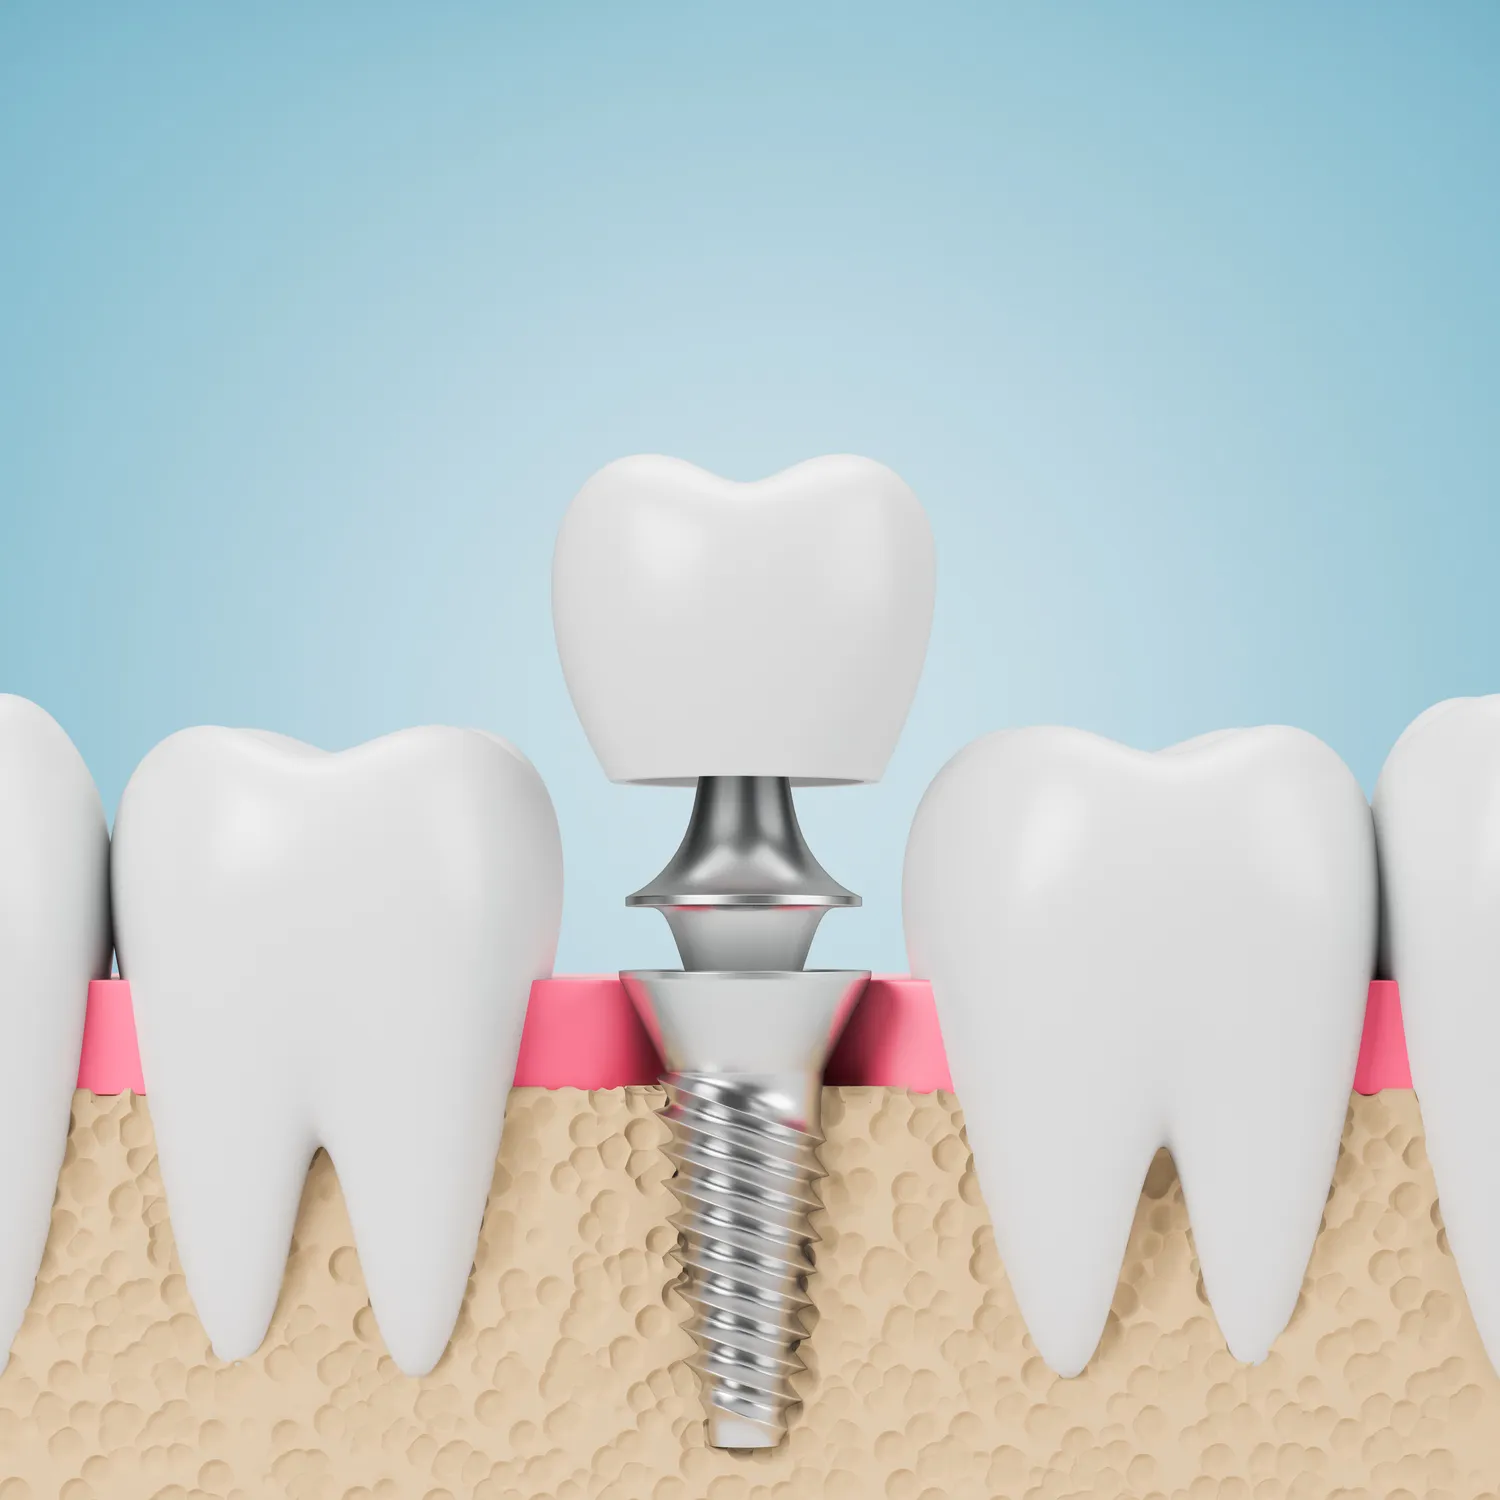

Inwestowanie w nowoczesne usługi stomatologiczne w Nysie przynosi wiele korzyści zarówno zdrowotnych, jak i estetycznych. Nowoczesne technologie stosowane przez dentystów pozwalają na szybsze i mniej inwazyjne leczenie różnych schorzeń jamy ustnej. Przykładem mogą być cyfrowe zdjęcia rentgenowskie, które umożliwiają dokładną diagnostykę przy minimalnym narażeniu pacjenta na promieniowanie. Ponadto nowoczesne materiały używane do plombowania czy koron są bardziej trwałe i estetyczne niż te stosowane wcześniej, co przekłada się na lepszy wygląd uśmiechu pacjenta. Warto także zwrócić uwagę na rozwój ortodoncji i dostępność aparatów ortodontycznych o estetycznym wyglądzie, które są mniej widoczne niż tradycyjne metalowe aparaty. Inwestycja w zdrowe zęby to nie tylko kwestia estetyki, ale przede wszystkim zdrowia ogólnego organizmu. Problemy stomatologiczne mogą wpływać na samopoczucie psychiczne oraz jakość życia codziennego.

W Nysie stomatolodzy coraz częściej korzystają z nowoczesnych technologii, które znacznie poprawiają jakość leczenia oraz komfort pacjentów. Jednym z najważniejszych osiągnięć w dziedzinie stomatologii jest wprowadzenie cyfrowego obrazowania, które pozwala na dokładną diagnostykę i planowanie leczenia. Dzięki temu lekarze mogą precyzyjnie ocenić stan uzębienia pacjenta oraz zaplanować odpowiednie zabiegi. Kolejną innowacją są systemy CAD/CAM, które umożliwiają projektowanie i produkcję koron, mostów czy wkładów bezpośrednio w gabinecie. Taki proces znacznie skraca czas oczekiwania na wykonanie protetyki, a także zwiększa jej precyzję. Warto również wspomnieć o laserach stomatologicznych, które są wykorzystywane do leczenia chorób dziąseł oraz przeprowadzania zabiegów chirurgicznych. Lasery minimalizują ból i krwawienie, co sprawia, że pacjenci czują się bardziej komfortowo podczas wizyt. Dodatkowo, wiele gabinetów w Nysie inwestuje w sprzęt do wybielania zębów, który pozwala na osiągnięcie szybkich i trwałych efektów estetycznych.